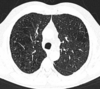

Q

A

Consolidación alveolar